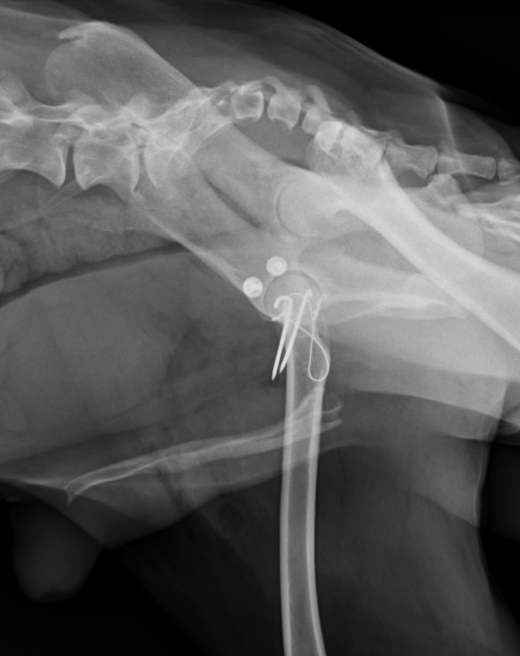

尾腹側脱臼では上記のワッシャーの方法は使用できず、トグルピン法か創外固定法、大腿骨頭切除の方法を用います。トグルピン方は、骨盤臼に穴を開け、そこにトグルピンと呼ばれる特殊な形のピンを挿入し、そこに引っ掛けた人工靭帯を、大腿骨に貫通させた穴に通して固定する方法です。この方法も2週間ほど維持できれば安定化していきます。